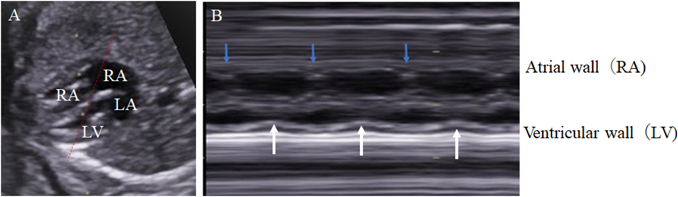

3) Evaluation of Ventricular Systolic Function

1. Fractional Shortening of the Ventricular Inner Diameter

Ventricular contractility is evaluated using the shortening rate of each ventricle. The cursor of the ultrasonography device is placed perpendicular to the septum beneath the AV valve in the 4CV. The movements of the mitral and the tricuspid valves are recorded simultaneously on M mode. This is helpful to identify systolic and diastolic phases. Fractional shortening (FS) is calculated with the difference between the end-diastolic and the end-systolic diameters of the ventricular cavity divided by the end-diastolic diameter.

FS=(end-diastolic inner diameter−end-systolic inner diameter)/end-diastolic inner diameter

The normal FS range (0.28–0.40) is independent of gestational age.90) If the position of a fetus renders the assessment of the ventricular size difficult, the modified Simpson method can be applied for determining the contraction rate tracing the ventricular cavity.91) Measurement errors, which could be rather large in fetal geometry, need attention when calculating FS whichever the methods are chosen.